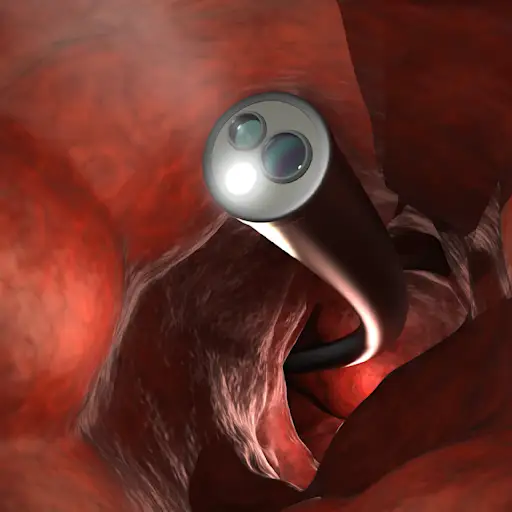

它是如何工作的

在结肠镜检查期间,医生将一个柔性相机插入到您的冒号中,以寻找任何异常增长的迹象。“我们正在寻找的是息肉,”Issaka博士说。“这些息肉是癌症的小生长。我们也在寻找早期癌症。“然后,医生可以在变大之前快速消除这些生长。您需要做肠道准备 - 这意味着在前一天饮用液体泻药清除您的结肠。股票在软卫生纸和阅读材料上。您还需要有人从程序中推动您回家。